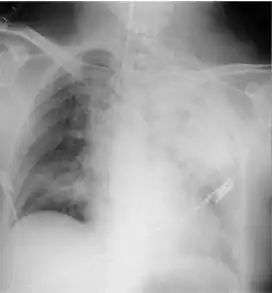

- Radiographic film